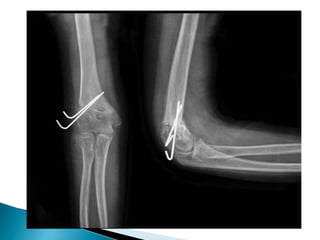

 Fixed with 2 kirschner wire (k-wire)

 4 TO6 cm longitudinal incision over lateral distal humerus  Between brachioradialis and triceps muscles  Coronoid fossa exposed circuferentially  Line of osteotomy make  Osteotomy made  Preserve the medial cortical hinge  Fixed with 2 kirschner wire (k-wire)  Long arm cast applied with elbow flex 90 deg